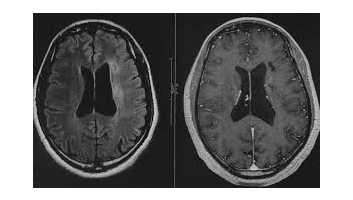

L'imagerie par résonance magnétique (IRM) est une technique d'imagerie médicale permettant d'obtenir des vues 2D ou 3D de l'intérieur du corps de façon non invasive avec une résolution en contraste relativement élevée. L'IRM repose sur le principe de la résonance magnétique nucléaire (RMN) qui utilise les propriétés quantiques des noyaux atomiques pour la spectroscopie en analyse chimique. L'IRM nécessite un champ magnétique puissant et stable produit par un aimant supraconducteur qui crée une magnétisation des tissus par alignement des moments magnétiques de spin. Des champs magnétiques oscillants plus faibles, dits radiofréquence, sont alors appliqués de façon à légèrement modifier cet alignement et produire un phénomène de précession qui donne lieu à un signal électromagnétique mesurable. La spécificité de l'IRM consiste à localiser précisément dans l'espace l'origine de ce signal RMN en appliquant des champs magnétiques non uniformes, des « gradients », qui vont induire des fréquences de précession légèrement différentes en fonction de la position des atomes dans ces gradients.

Il est alors possible de reconstruire une image en deux dimensions puis en trois dimensions de la composition chimique et donc de la nature des tissus biologiques explorés.